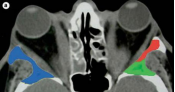

眶CT:彩色示眶减压手术需去除的骨壁